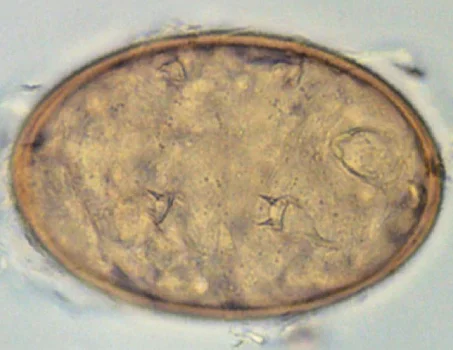

Für den Nachweis von L. serrata eignen sich 2 verschiedene Methoden. Zum einen können die Eier des Parasiten (mit durchsichtiger Außenhülle) in einem Nasenschleim-Abstrich nachgewiesen werden. Zum anderen kann ein Nachweis mittels Koproskopie per Flotationsverfahren erfolgen, wobei die durchsichtige Außenhülle der Eier meist verloren geht. Hierzu sollte der Kot im Verhältnis 1:10 mit 5%iger Kalilauge vermischt werden. Danach erfolgt ein mehrmaliges Sedimentieren in Wasser und zuletzt wird das Sediment in Zinkchloridlösung flotiert. Die ovalen Eier (90 × 70 µm) enthalten die Primärlarve, deren stummelige Extremitäten paarige Chitinhaken tragen (Abb. 1).